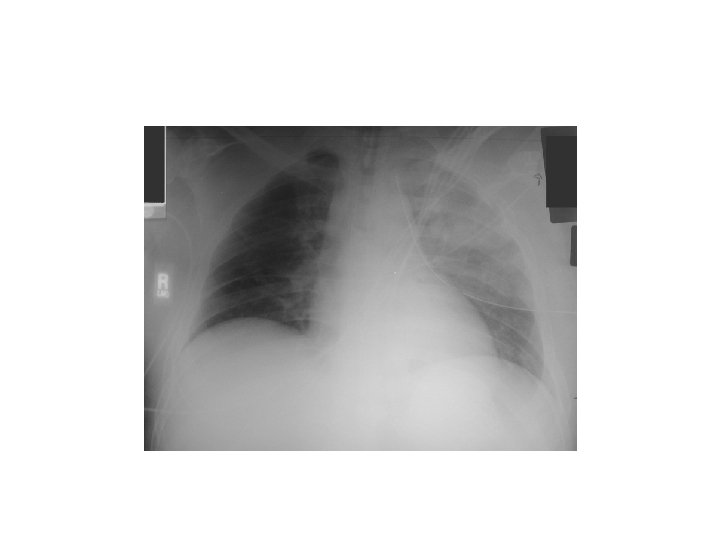

Tumors Left lower zone We say zone not lobe in X-Ray … because we can’t confirm the lobe except by other modality. . E. g. lateral Xray

Clinical Features § Asymptomatic § Symptomatic ü General : loss of appetite , fever , loss of weight , fatigue. ü Lung : cough is the commonest , occures in half of the pt !, Haemoptysis , sputum production , SOB, pain ü Pressure symptomes on Surrounding structures : § Rec. L. nerve : chocking ( )ﺗﺘﺸﺮﺩﻕ on drinking , hoarsness. § Oesophagus : dysphagia. § C 8, T 1 nerve : arm pain or numbness , brachial plexus § Sympathetic especially injury to satellite ganglion (1 st sympathetic ganglion): Horner's syndrome ( ptosis , Anhidrosis , enophthalmos … etc ) § Pleura § SVC : superior vena cava obstruction syndrome , Shortness of breath is the most common symptom, followed by face or arm swelling § Para. Neoplastic Syndrome (next slide)

§ distal (para-neoplastic syndrome) - Squemous cell carcinoma. § § § PTH ADH ACTH Hypertrophic pulmonary osteoathropathy (HPOA) : pain and swelling of joints. not responsive for any ttt. Once the tumor removed , all the symp. Improved Hypercalcemia , hyponatremia , fluid retention. (cushing syndrome) Investigations § § § CXR Trans-thoracic needle aspiration CT Scan Bronchoscopy MRI : Poor modality in Lung cancers in general ! If there is involvement of the major structures in the apex ( brachial plexus , vertebral column , spinal canal , apex , spine ) Staging : ﻧﻌﺘﻤﺪ ﻋﻠﻴﻪ (see table)